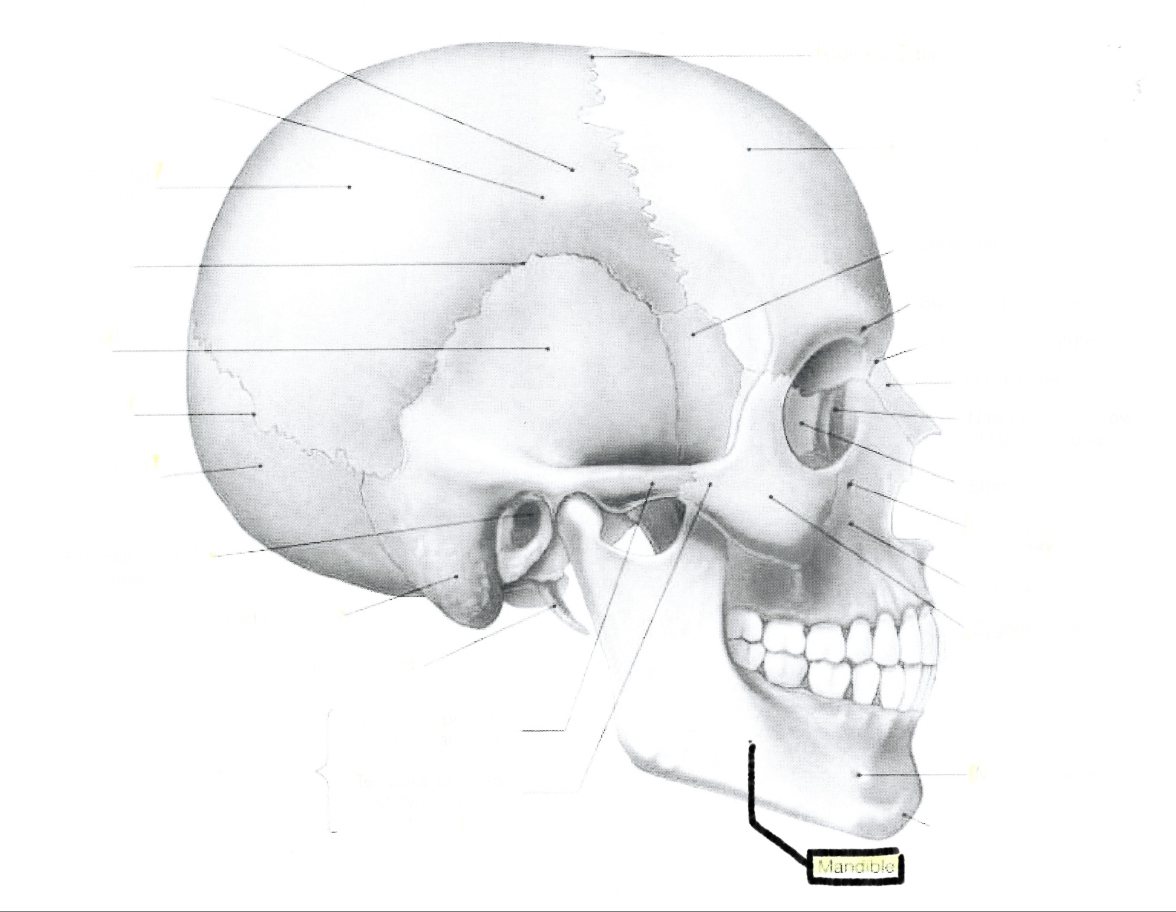

What is this?

Mandible